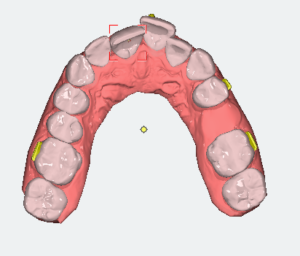

Analizę przemieszczeń zębów w zakresie mezjalizacji trzonowców w szczęce oraz przemieszczenie przedtrzonowca górnego rozpoczęto dopiero po uzupełnieniu zlecenia o analizę zdjęcia panoramicznego oraz badań dodatkowych. Opisano trzy opcje leczenia tego pacjenta. Pierwsza propozycja obejmowała brak mezjalizacji d. 26 i d.27; dystalizację w zakresie wybranych zębów. Druga propozycja obejmowała minimalną dystalizację drugiej ćwiartki łuku zębowego. Trzecia propozycja obejmowała sekwencyjną mezjalizację d. 26 oraz d. 27.

Cyfrowy plan leczenia przeanalizowano pod kątem osiągnięcia klinicznego celu zaplanowanego przez lekarza. Zaplanowana na cyfrowym planie leczenia mezjalizacja nie uwzględniała rekomendowanego sekwencyjnego przemieszczania zębów. Oznaczało to bardzo mało prawdopodobne zajście tych ruchów w jamie ustnej u pacjenta. Opisano lekarzowi, na czym polega sekwencyjna mezjalizacja zębów i jak zaprojektować ją w nowym planie leczenia. Zwrócono uwagę, że tego typu przemieszczenia zębów są bardzo wymagające, dlatego lekarze do zwiększenia możliwości ich zajścia stosują np. miniimplanty ortodontyczne. Opisano wpływ ilości i jakości attachmentów na zwiększenie przewidywalności ruchów zębowych.

- Zmodyfikować sekwencje mezjalizacji trzonowców.

- Plany leczenia dzielić na części, w których przemieszczane są pojedyncze zęby, a nie wszystkie zęby w maksymalnych zakresach jednocześnie.